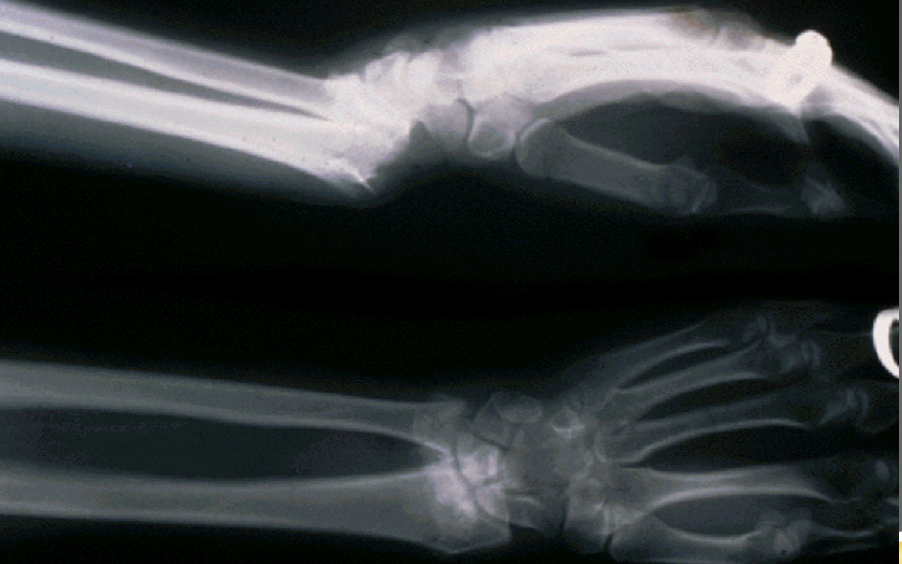

colles fracture

dorsal displacement of distal segment → hand goes dorsal

happens from a FOOSH → distal radius fracture

smith fracture

volar displacement of distal segment → hand moves anterior

happens when you fall and land on the back of your hand